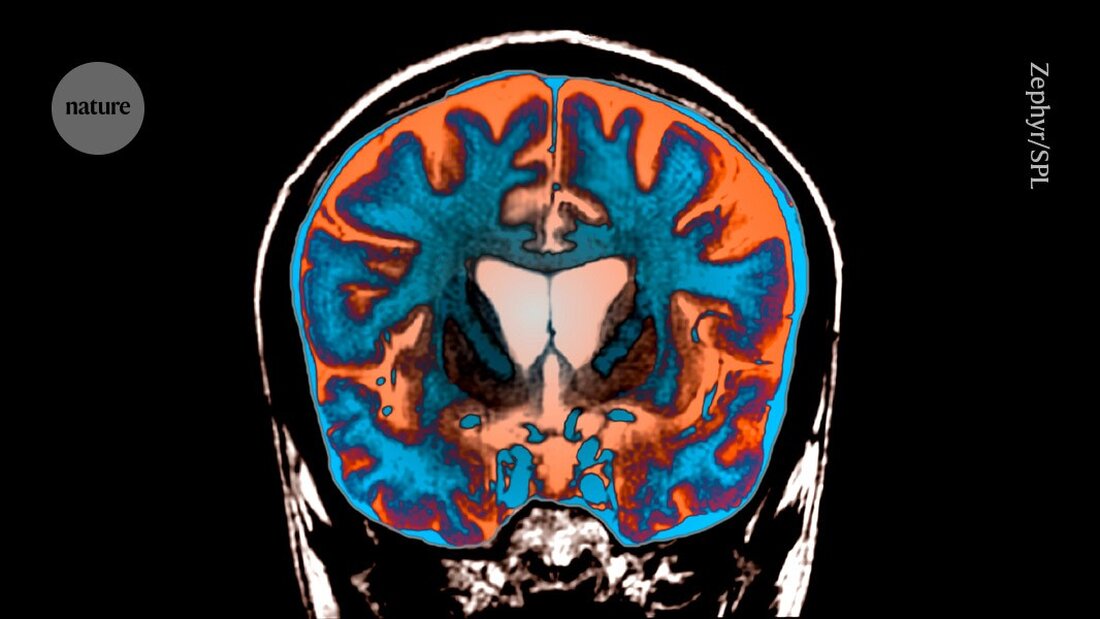

Enthüllt: Warum das tödliche Huntington-Gen so lange braucht, um Schaden zu verursachen

Erfahren Sie, warum das Huntington-Gen erst spät schädliche Auswirkungen zeigt, und welche neuen Erkenntnisse dazu gewonnen wurden.